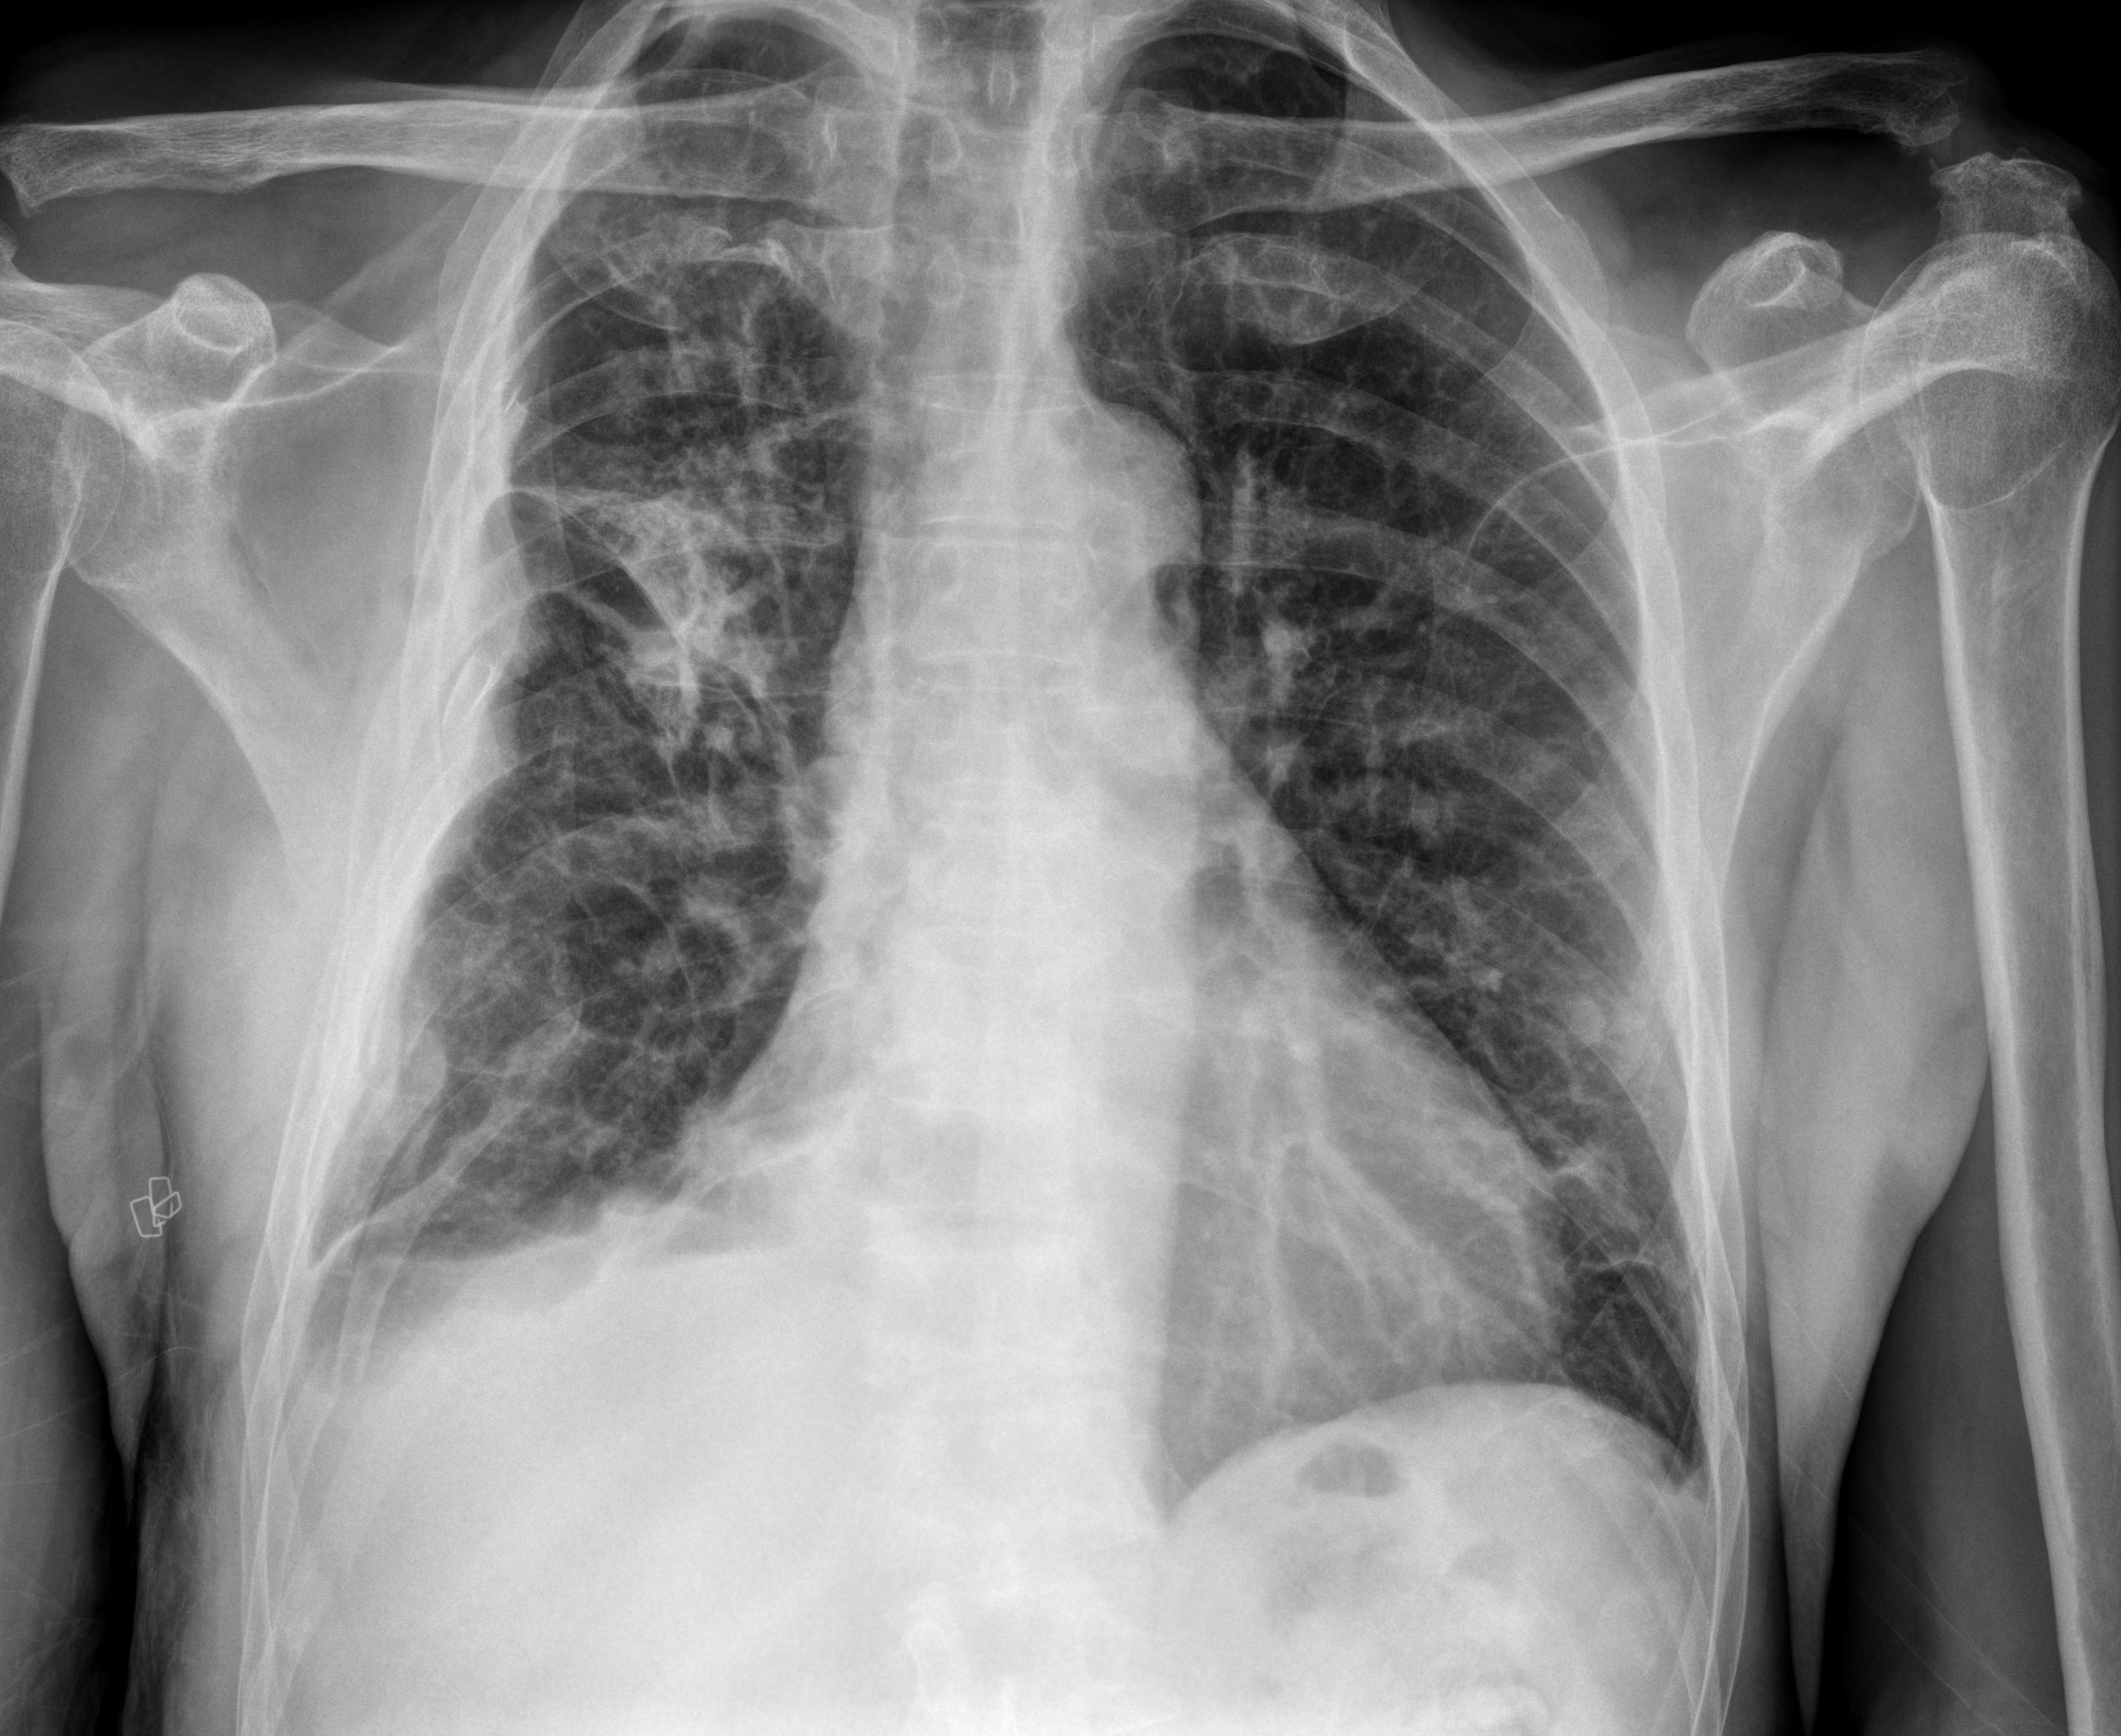

1 Tórax portátil